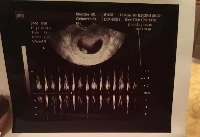

Terhesnapló10 - Liza: Dobog a szíve! (8. hét)

Elmentünk az első kontroll vizsgálatra a szülészorvosunkhoz. Furcsa találkozás volt. Én úgy mentem oda, hogy előtte egyeztettem az asszisztenssel, minden információt megosztottam vele (mikor volt az utolsó menstruációm, hány... »